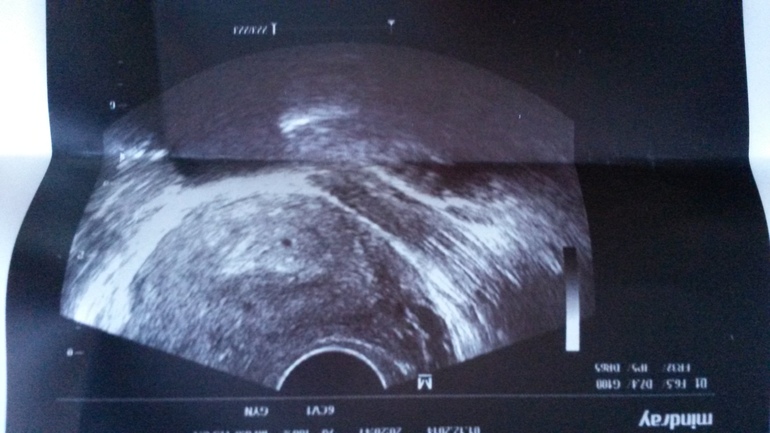

На 18 Дпо или 4 Дз мою бусинку нашли в матке 3 мм. Я очень рада,что моя крошка на месте)).

Но в общем настрой у меня хороший. Верю что все будет у нас хорошо. И напоследок фото моей крошки

А я тоже вижу еще точку. Но это наверно что то другое. Мне узистка сказала,что есть признаки какие то,что у меня возможна двойня в принципе. Но сейчас 1 плодное яйцо. Как думаешь могла она ошибиться?

на таком сроке могла.смотри, твоя чёрная точка на фото находится в как бы пузыре, видим чёткие ровные контуры . слева от неё тоже точка чёрная в таком же пузыре имеет ровные чёткие контуры. блин у меня даже ребёнок видит там двоих)))на фото выглядит как глаза))))

Я думала матка беловатая такая на узи. А в ней вроде одна точка.

Что-то я не готова пока. Склоняюсь все таки что один там. А вторая точка это мой богатый внутренний мир))

Май,разве я не правильно говорю маленькая белая область овальная это и есть матка? А вторая точка за этой областью.

Все посмотрела. Спасибо. Я вообще не туда смотрела на вторую))) А ту которую ты увидела вторую точку, что-то она совсем какая-то невнятная. Мне кажется это что-то другое))

в 8 недель точно будет видно сколько там) в любом случае двойня это двойное счастье))))